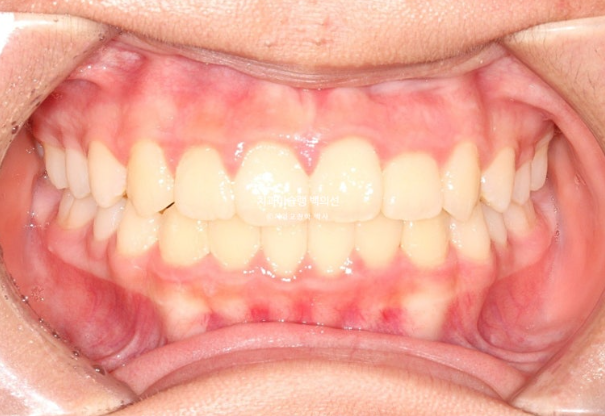

이제 전 후 비교해 보겠습니다.

총 치료기간은 1년 6개월이고 중간에 중심선 이슈로 잠시 쉬는 시간이 4개월 있었습니다.

재제작은 총 2회 했습니다.

24.02~25.07

치료결과가 어린이 교정이 아닌 정식 성인교정 치료 결과에 준한만큼 유지장치도 철저히 들어갑니다.

어긋난 중심선이 맞아졌으며 기울어진 앞니 치축도 좋아졌습니다.

앞니가 깊게 물리는 과개교합도 좋아졌습니다.

25.07